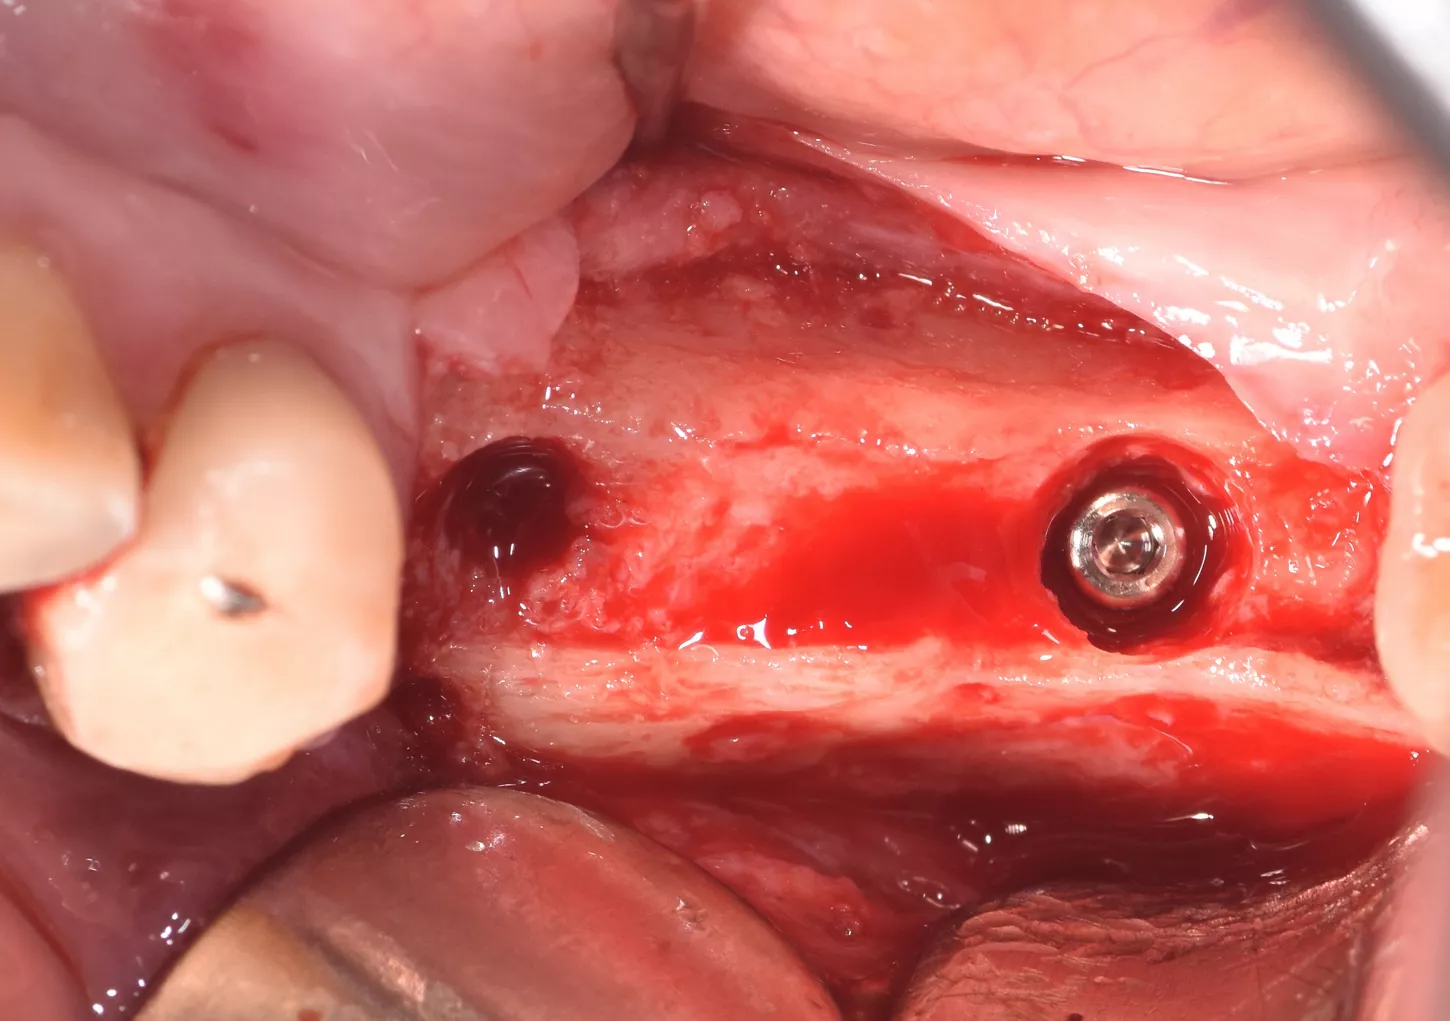

5. Five months later, the site was reopened and two Axiom X3® Ø4 x 10 mm implants were placed in positions 35 and 36. The implants were positioned infra-crestally using the submerged technique with a torque of 25 Ncm.

6 . Infra crestal position of the implants in the fully regenerated bone.